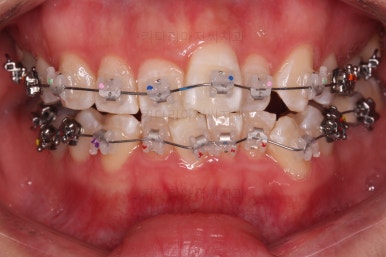

처음 장치를 부착한 사진입니다.

이번에 동래교정치과 선택한 장치는 엠파워 클리어라고 하는 자가결찰 세라믹 장치인데요.

흔히들 클리피씨라고 알고 계신 장치의 종류입니다.

엠파워와 클리피는 제조국만 미국, 일본으로 차이가 나고 큰 틀에서는 같은 장치라고 보시면 됩니다.

동래교정치과 장치 부착 사진인데요.

세라믹이라 비교적 장치가 많이 눈에 띄지 않고요.

입은 장치의 볼륨감으로 약간 튀어나오는 모습입니다.